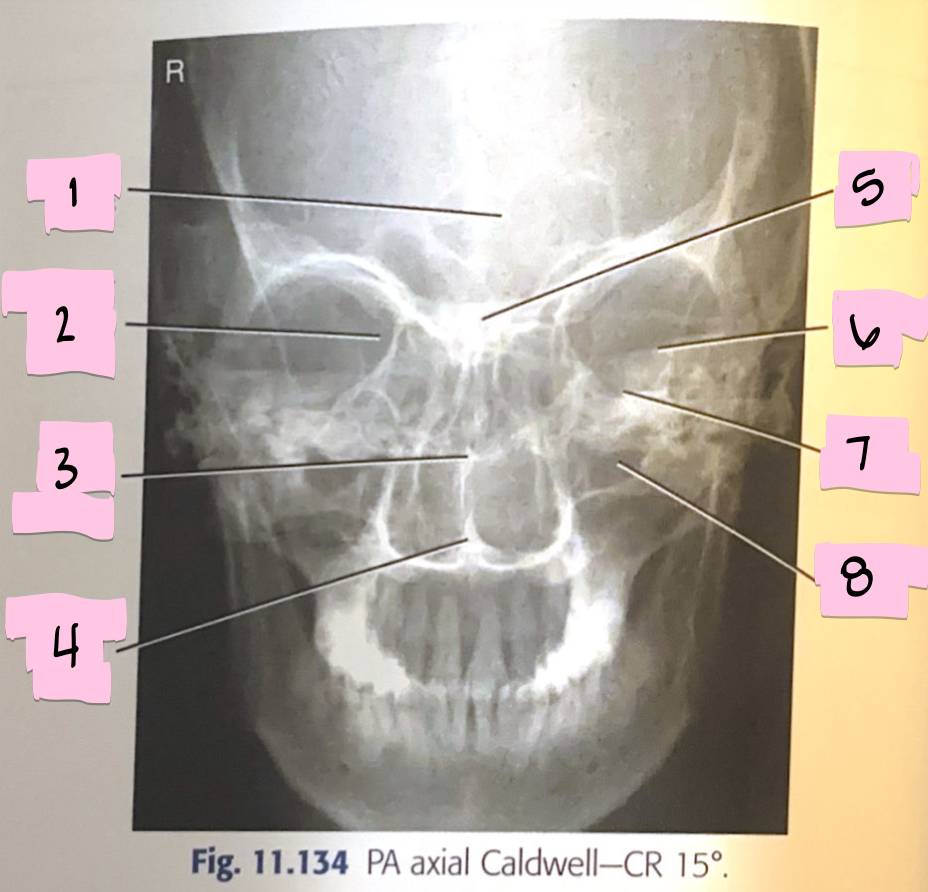

What is 1 pointing to?

Frontal sinus

What is 2 pointing to?

Superior orbital fissure

What is 3 pointing to?

Bony nasal septum

What is 4 pointing to?

Anterior nasal spine

What is 5 pointing to?

Crista galli

What is 6 pointing to?

Petrous ridge

What is 7 pointing to?

Floor of orbit

What is 8 pointing to?

Maxillary sinus